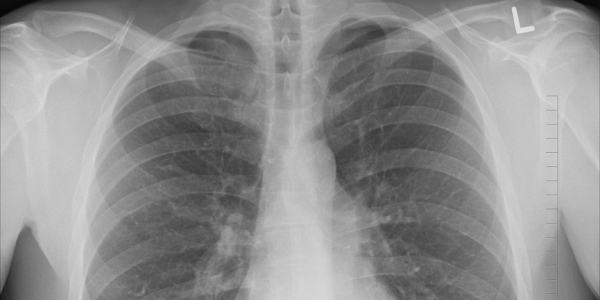

A MSD anunciou recentemente os resultados do KEYNOTE-189, um estudo piloto de Fase III que avalia pembrolizumab, terapia anti-PD-1 da MSD, em combinação com pemetrexed e cisplatina ou carboplatina para o tratamento de primeira linha do cancro do pulmão de células não-pequenas (CPCNP) metastático. Os resultados demonstraram que a combinação de quimioterapia pembrolizumab-pemetrexed-platina melhorou significativamente a sobrevivência global (OS), reduzindo o risco de morte para metade em comparação com a quimioterapia isolada.